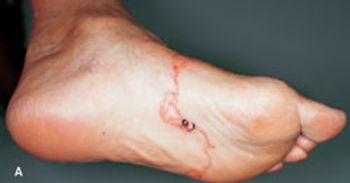

A 69-year-old man with stage II chronic kidney disease due to hypertension fell from his bicycle and presented to the emergency department (ED) with abrasions, ecchymoses, and a 3-cm laceration on his right leg. The patient was an avid cyclist. His wounds were cleaned and the laceration sutured. There were no fractures, and the patient was discharged home.